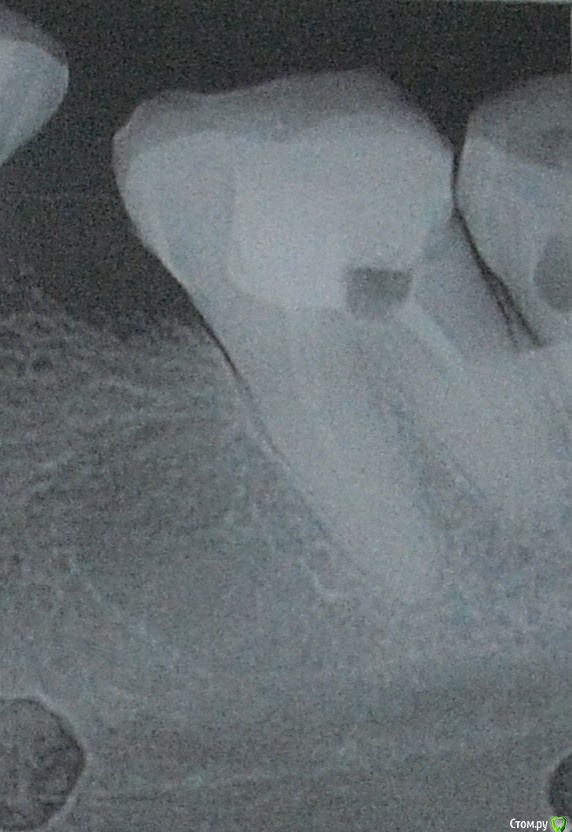

usersha Опубликовано 1 августа, 2019 Поделиться Опубликовано 1 августа, 2019 Здравствуйте! 10 дней назад у меня выступил флюс то есть десна между 7 и 8 зубом слева внизу отекла и появился гнойничек. До этого была боль пульсирующая или как будто распирающая. После того появился флюс боль практически прошла. У врача на приеме сделали снимок. Я думала что причина в 8 зубе так как боль усиливалась при нажатии. Но потом когда боль прошла то и при нажатии боли нет. По снимку врач сказала что корни нормальные и проблема в десне может быть поранила. Хирург сделал надрез сказал чтобы выходила инфекция. Дренаж не ставил. Я полоскала содой солью и пила амоксициллин 8 дней. Отек стал спадать было видно как образуется гнойное типа налета и выходит..... где то дня 4 назад десна стала немного побаливать и я добавила левомеколь - 3 раза в день... и периодически из этого надреза появляется белый налет (гной) потом при полоскании отскакивает. Опухоль в основном спала,но десна слегка увеличена. В основном десна не болит если не теребить ее. Как долго выходит инфекция и проходит флюс? Вторая неделя пошла это долго или это нормальные сроки? И еще вопрос. Пломба у 7 зуба стоит так что с внутренней стороны межзубное пространство забито пломбой и она упирается в десну. Я прочитала что нависающий край пломбы может травмировать десну. Один из способов проверить - зубная нить которая не должна цепляться. Как раз если провести нитью то у самой десны нить как бы цепляется как за крючок что ли. Могла ли эта пломба в межзубном пространстве давящая на десну привести к флюсу? Сейчас там где с внутренней стороны пломба давит в межзубном пространстве я чувствую дискомфорт и немного болезненно у десны. Флюс у меня с внешней стороны ( то есть со стороны щеки) он был расположен как-то прям между зубами 7 и 8 со смещением отечности в сторону 8 зуба. Может ли врач убрать пломбу в межзубном пространстве нависающий край без переделывания всей пломбы? Заранее большое спасибо за помощь! PS первый снимок 7 и 8 зубы, второй снимок 7 зуб и часть 8 Ссылка на комментарий

red_butler Опубликовано 2 августа, 2019 Поделиться Опубликовано 2 августа, 2019 Спасибо за ответ! Скажите а зачем удалять зуб мудрости если он не болит и как сказала врач там корни нормальные? флюс скорее от травмы либо зубной щеткой десны либо от постоянного пломбы в межзубном пространствеВосьмой зуб сильно разрушен, корневые каналы полноценно не пролечены. Контактного пункта с седьмым зубом нет, это привело к воспалению десны и рецидиву кариеса на седьмом зубе. Оставляя зуб мудрости Вы приближаете конец седьмого зуба. 2 Ссылка на комментарий

usersha Опубликовано 2 августа, 2019 Автор Поделиться Опубликовано 2 августа, 2019 Восьмой зуб сильно разрушен, корневые каналы полноценно не пролечены. Контактного пункта с седьмым зубом нет, это привело к воспалению десны и рецидиву кариеса на седьмом зубе. Оставляя зуб мудрости Вы приближаете конец седьмого зуба.спасибо большое за ответ! подскажите еще пожалуйста удалять нужно когда флюс пройдет полностью? просто уже дней 10 но до конца десна не восстановилась... опухоль спала осталось совсем немного и из того разреза что делал хирург периодически появляется гной - полощу содой солью иногда хлоргексидином мажу левомеколем. сколько должно по времени проходить флюс?может ли быть такое что десна не проходит так долго потому что мне не ставили дренаж? Ссылка на комментарий